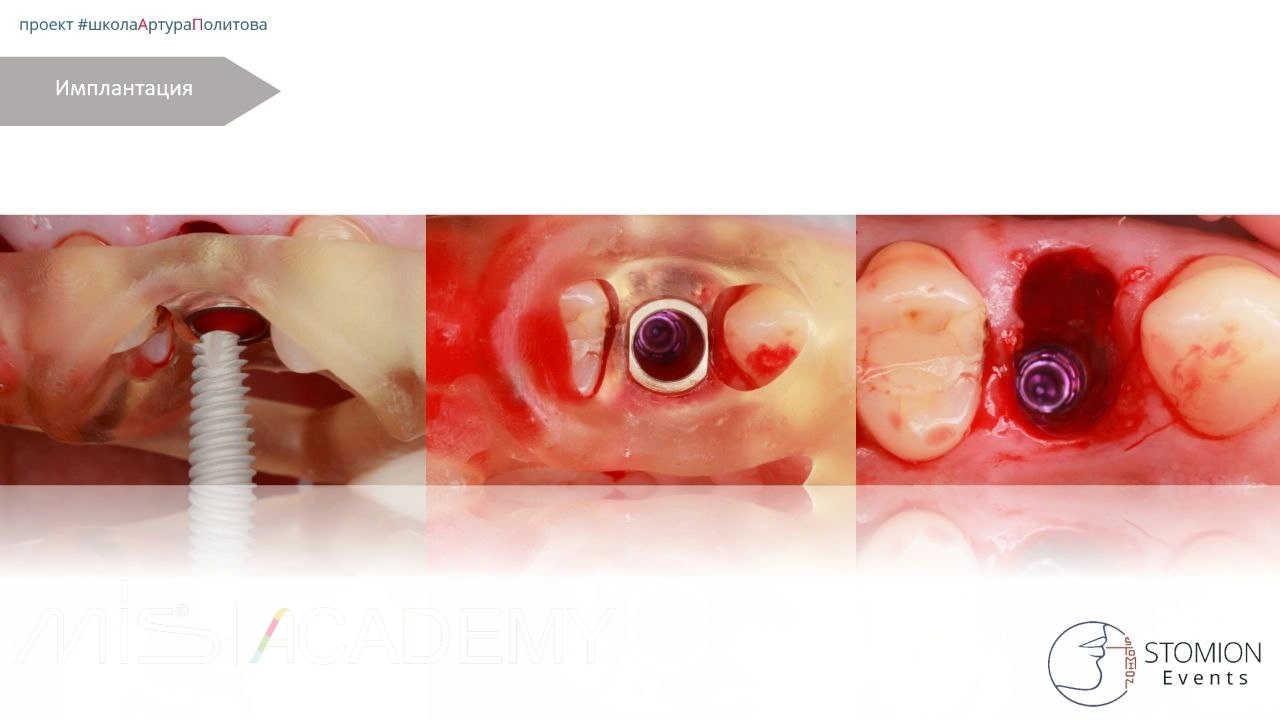

— Одномоментная имплантация MIS C1 3,75х13 в небную лунку, торк 45+

— CONNECT абатмент 3мм, торк 30 Н/см

— IDR

— СТТ

— Немедленная нагрузка